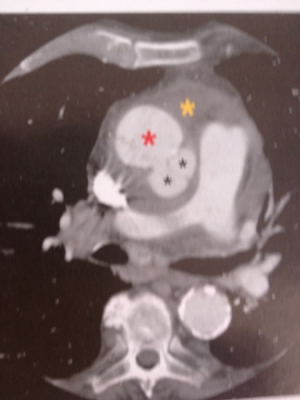

Διέρχεται αίμα διά μέσου ρήξης του μέσου χιτώνα,διαχωρίζοντας τον αορτικό αυλό κατά μήκος της αορτής.Επομένος έχουμε το διαχωρισμό τύπου Α κατά Stanford:περιλαμβάνει την ανιούσα αορτή,το αορτικό τόξο και μερικές φορές τη θωρακική αορτή.

Μετά την ενδοφλέβια χορήγηση σκιαγραφικής ουσίας ελέγχεται η παρουσία διαχωρισμένου έσω χιτώνα μεταξύ αληθούς και ψευδούς αυλού,καθυστερημένη πλήρωση του ψευδούς αυλού ή πλήρης απουσία πλήρωσης λόγω θρόμβωσης,συμπίεση του αληθούς από το ψευδή αυλό και εκτίμηση της έκτασης του διαχωρισμού.